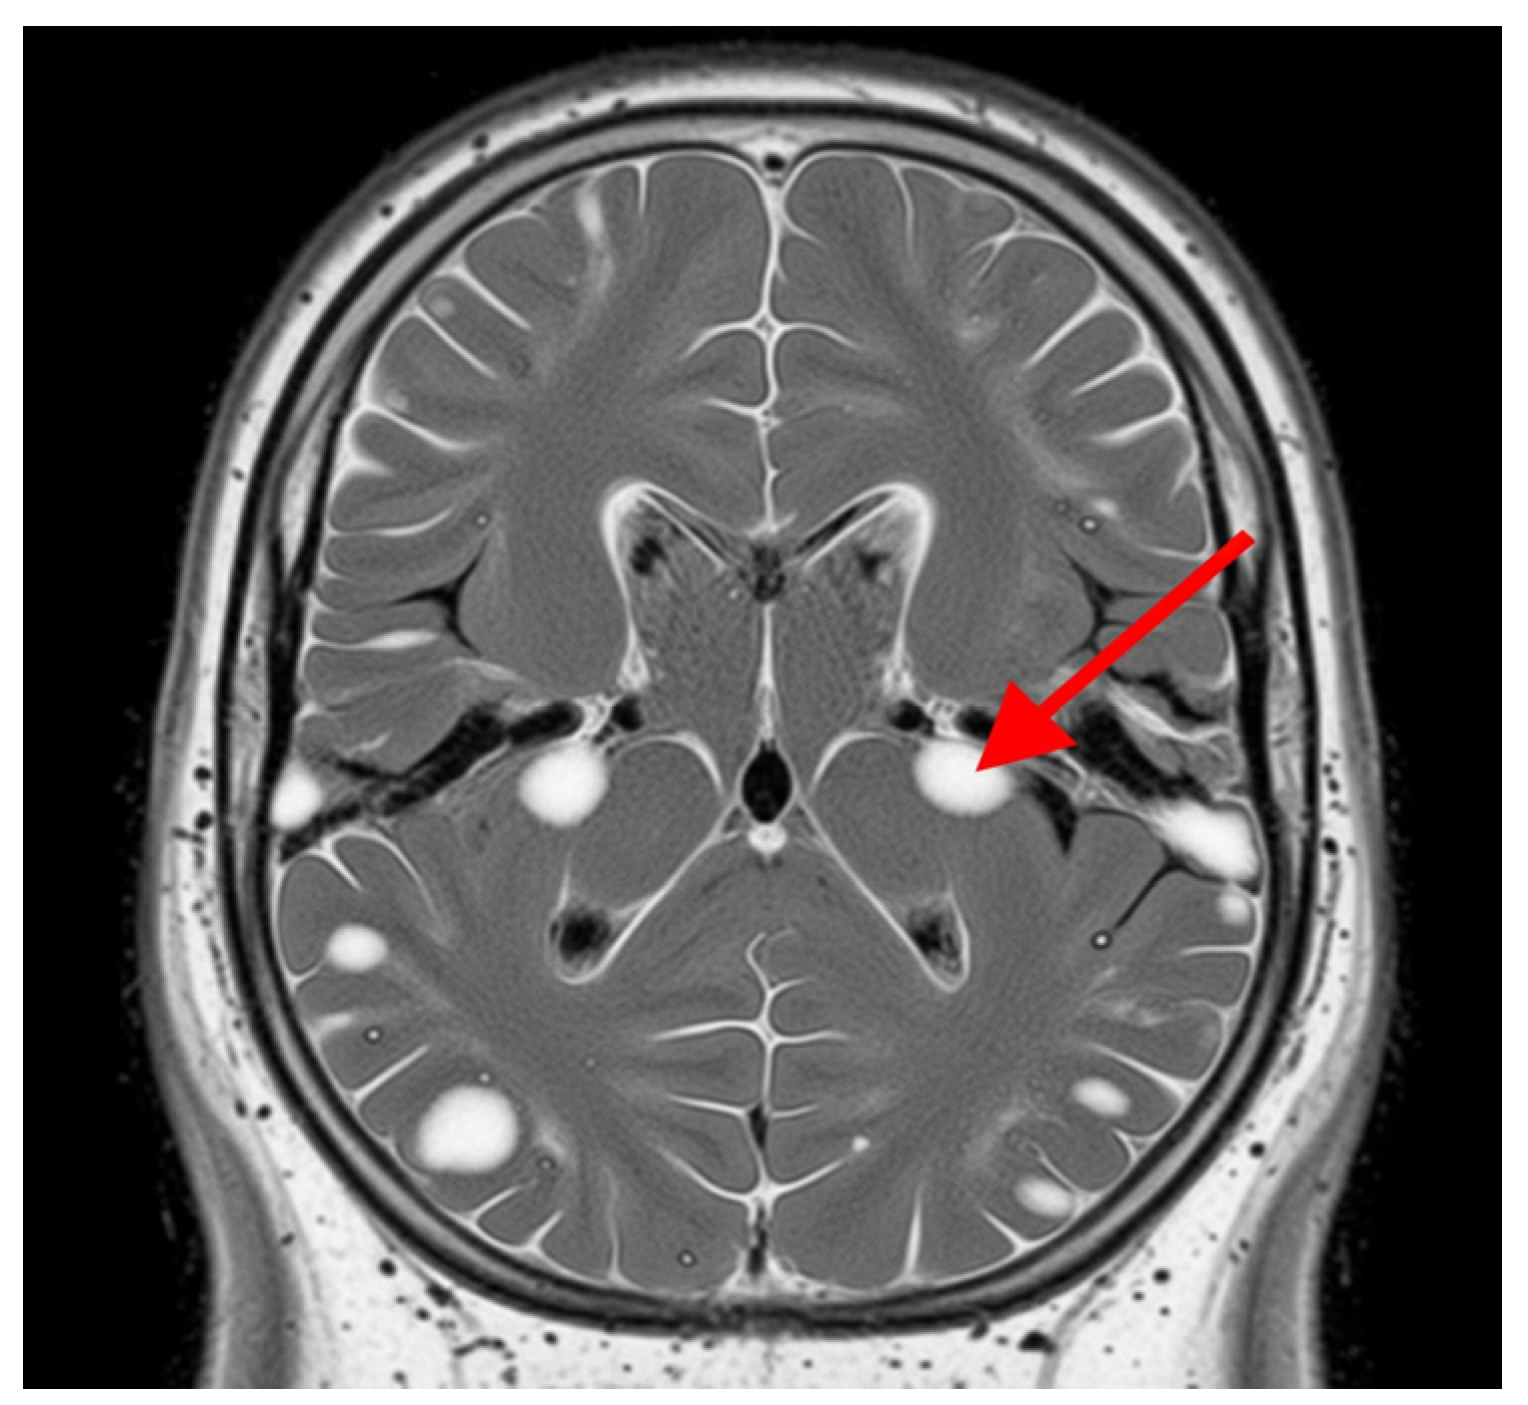

6.

Axonal loss, a critical driver of disability progression in SPMS, is associated with irreversible neurological deficits in patients with SPMS. MRI indirectly detects axonal loss by evaluating brain atrophy, lesion burden, and altered diffusion patterns. Brain atrophy, reflected by reductions in brain volume, particularly in the grey matter (GM) and white matter (WM), is a hallmark of significant axonal degeneration and neuronal loss. Quantitative MRI techniques, including the normalized brain volume (NBV), normalized cortical GM volume (NCGMV), and normalized WM volume (NWMV), are used to assess this loss. It has been shown that patients with SPMS exhibit more pronounced brain volume reduction compared to those with RRMS [6]. Furthermore, diffusion tensor imaging (DTI) offers additional insights into axonal damage through parameters such as fractional anisotropy (FA) and mean diffusivity (MD). These metrics reflect the microstructural integrity within the white matter tracts. In SPMS, decreased FA values in regions such as the fornix and medial lemniscus have been correlated with cognitive impairment and disease progression, underscoring the clinical relevance of axonal integrity as revealed by advanced imaging techniques, Figure 1 [7].

Figure 1. Axonal loss due to demyelination. Over time, this leads to brain atrophy and irreversible neurological deficits.

Jcm 14 04114 g001